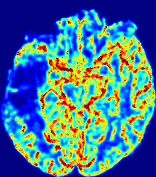

4.3.1 Advection Imaging via Advection-Diffusion

Slice #1Slice #2Slice #3Slice #4Slice #5Slice #6𝐕gt𝟐subscriptnormsuperscript𝐕gt2\|\bf{V}^{\text{gt}}\|_{2}Refer to captionRefer to captionRefer to captionRefer to captionRefer to captionRefer to caption𝐕est𝟐subscriptnormsuperscript𝐕est2\|\bf{V}^{\text{est}}\|_{2}Refer to captionRefer to captionRefer to captionRefer to captionRefer to captionRefer to captionRefer to caption1.51.51.51.21.21.20.90.90.90.60.60.60.30.30.30.00.00.0(mm/s)𝑚𝑚𝑠(mm/s)Destsuperscript𝐷estD^{\text{est}}Refer to captionRefer to captionRefer to captionRefer to captionRefer to captionRefer to captionRefer to caption0.0150.0150.0150.0120.0120.0120.0090.0090.0090.0060.0060.0060.0030.0030.0030.0000.0000.000(mm2/s)𝑚superscript𝑚2𝑠(mm^{2}/s)

Figure 14: PIANO identifiability testing: advection imaging via advection-diffusion. Top row shows 𝐕gt2subscriptnormsuperscript𝐕gt2\|{\bf{V}}^{\text{gt}}\|_{2} used for simulating ground truth pure advection. Rows below show the estimated 𝐕est2subscriptnormsuperscript𝐕est2\|{\bf{V}}^{\text{est}}\|_{2} and Destsuperscript𝐷estD^{\text{est}} on corresponding slices. Note that the plotted value scale for Destsuperscript𝐷estD^{\text{est}} is 0.01 of that for 𝐕gt2subscriptnormsuperscript𝐕gt2\|{\bf{V}}^{\text{gt}}\|_{2} and 𝐕est2subscriptnormsuperscript𝐕est2\|{\bf{V}}^{\text{est}}\|_{2}.

We use the same ‘Advection Imaging’ simulation of Sec. 4.2.1 as the concentration dataset for PIANO. However, instead of modeling pure advection (Eq. 15), we let PIANO estimate both velocity 𝐕estsuperscript𝐕est{\bf{V}}^{\text{est}} and diffusivity Destsuperscript𝐷estD^{\text{est}} via the advection-diffusion PDE (Eq. 2) underlying the proposed PIANO model. Fig. 14 shows the estimated 𝐕est2,subscriptnormsuperscript𝐕est2\|{\bf{V}}^{\text{est}}\|_{2}, and Destsuperscript𝐷estD^{\text{est}} fields for one patient. Although PIANO has the freedom to estimate both a velocity and a diffusivity field from pure advection, PIANO differentiates well between advection and diffusion: the estimated 𝐕est2subscriptnormsuperscript𝐕est2\|{\bf{V}}^{\text{est}}\|_{2} successfully reproduces the ground truth 𝐕gt2subscriptnormsuperscript𝐕gt2\|{\bf{V}}^{\text{gt}}\|_{2} governing the simulated advection process, just as it already did in the ‘Advection Imaging via Advection’ test (Fig. 12). More importantly, the estimated diffusivity Destsuperscript𝐷estD^{\text{est}} is orders of magnitudes smaller than 𝐕est2subscriptnormsuperscript𝐕est2\|{\bf{V}}^{\text{est}}\|_{2}, indicating the estimated diffusion is negligible compared to the estimated advection, which is highly consistent with the underlying pure advection of the simulated data.